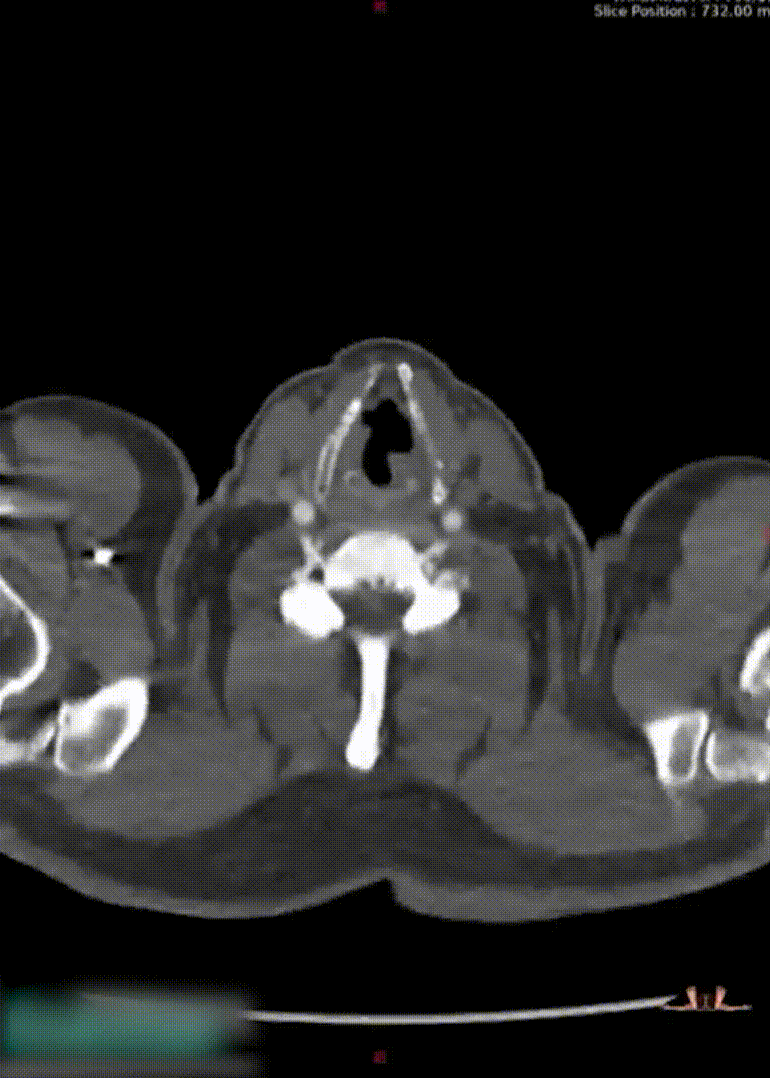

患者61岁,男性,因咳嗽、声音嘶哑及饮水呛咳3月余就诊,CTA发现“主动脉弓动脉瘤”(累及Z0-Z2区)。

术前CTA显示动脉瘤范围广泛,双侧髂总动脉纤细狭窄,入路困难;手术需同时重建无名动脉、左颈总动脉及左锁骨下动脉。